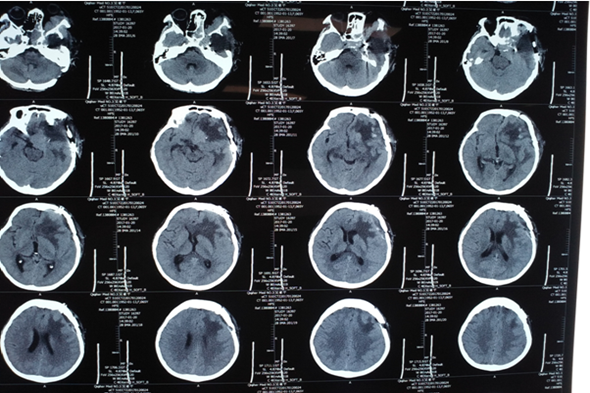

对于患复发性脑膜瘤的吴女士来说,这个冬天注定难以平静,说起吴女士的患病经历,还要从两年前说起,两年前,患者发病就诊于外地医院,头核磁共振检查诊断:颅内占位。随即行开颅手术,术后病理示脑膜瘤,患者恢复较好,未行放射、化疗等辅助治疗。术后一年复查时发现肿瘤再次复发。自觉左眼有发胀感,继之出现左眼突出,视力下降,同时伴有头部疼痛、进食差,随着病情进展,患者左眼视力完全丧失,当即在北京就医,行头MRI检查,结果显示为侵袭性脑膜瘤,肿瘤直径9cm大小,需手术治疗。吴女士几经周转,多方打听,最后得知我院成功治疗多例此类疾病,且效果良好,遂慕名来我院治疗。

术前MR